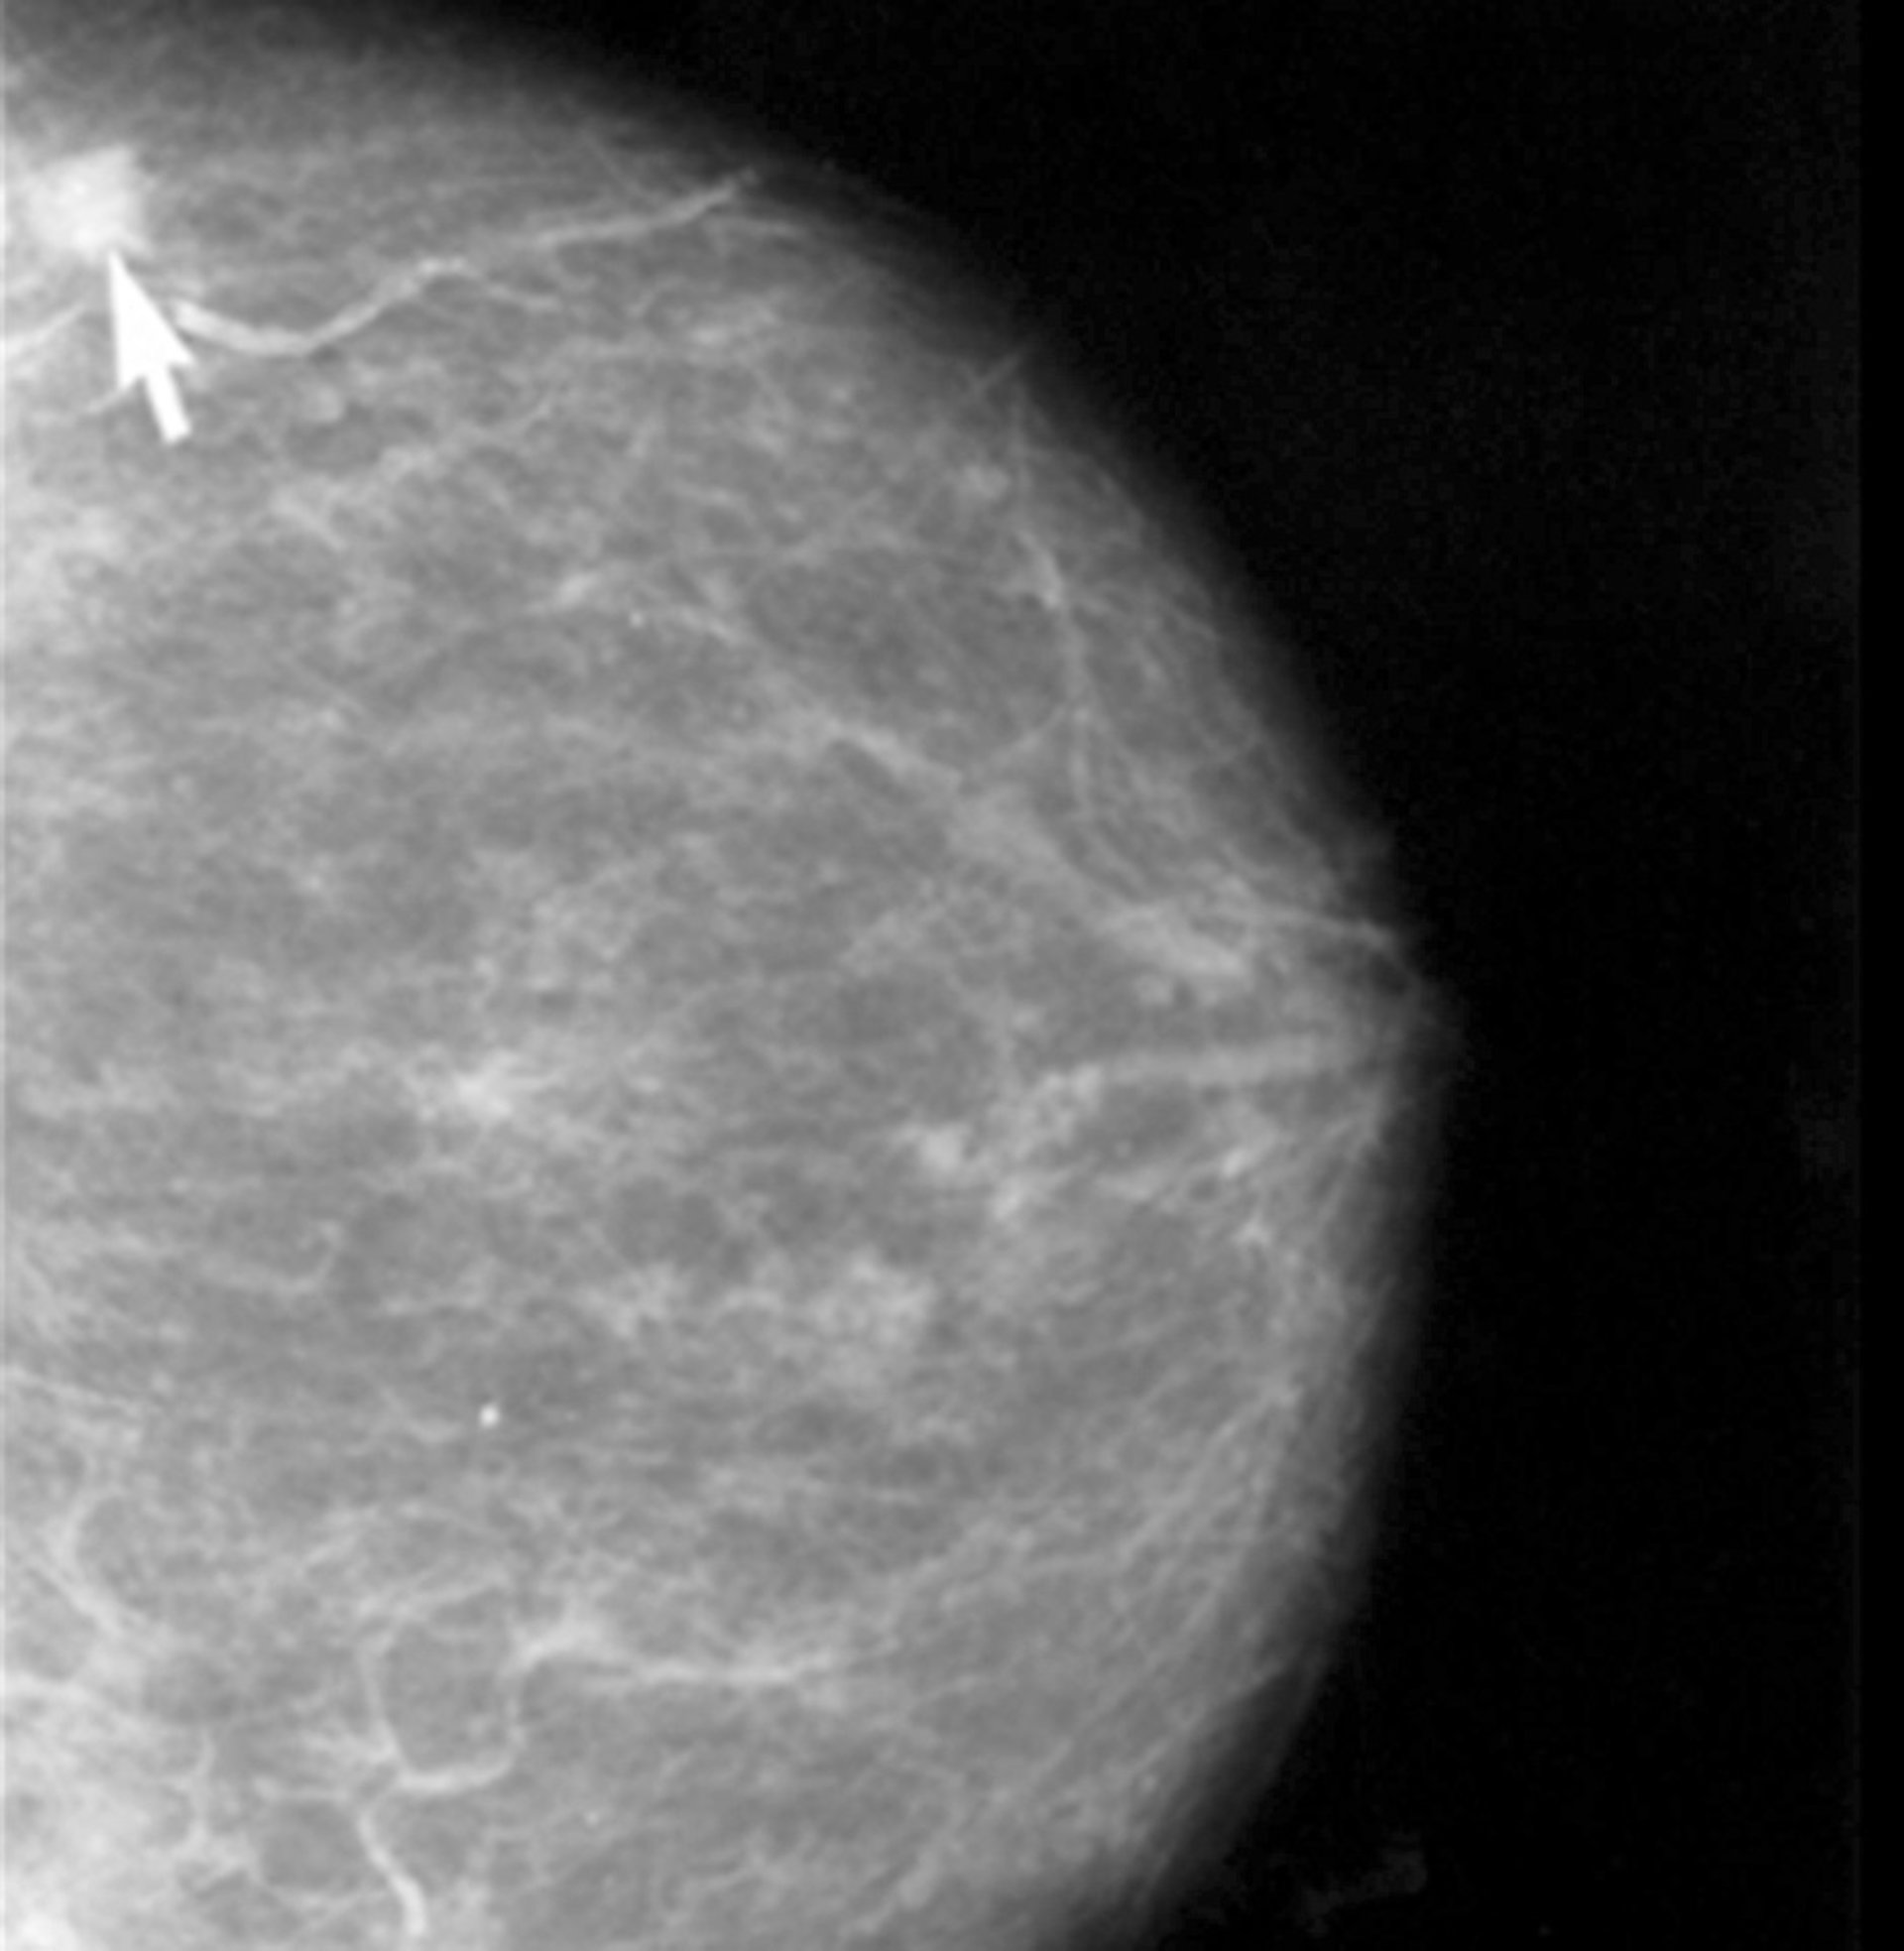

Alrededor de 2.100 de los 22.000 nuevos casos de cáncer de mama que se registran cada año en España se diagnostican en la Comunidad Valenciana, lo que supone algo más del 10 por ciento. En la mayoría de los casos se diagnostican en las 29 Unidades de Diagnóstico Precoz de las que se dispone en la autonomía, según los datos facilitados a raíz de la segunda reunión regional multidisciplinar del grupo SOLTI, dedicada al 'Abordaje multidisciplinar del tratamiento neoadyuvante del cáncer de mama'.

REDUCCIÓN DE LA MORTALIDAD

Gracias al trabajo de las 29 Unidades de Diagnóstico Precoz, de las mejoras en la cirugía, el tratamiento y también a la labor de las cinco Unidades de Consejo Genético de la Comunidad Valenciana, donde son visitadas aquellas familias con riesgo de presentar cáncer de mama hereditario, "la mortalidad por cáncer de mama en la Comunidad se ha reducido en torno a un 30 por ciento" en la última década, ha subrayado el doctor Gavilá.